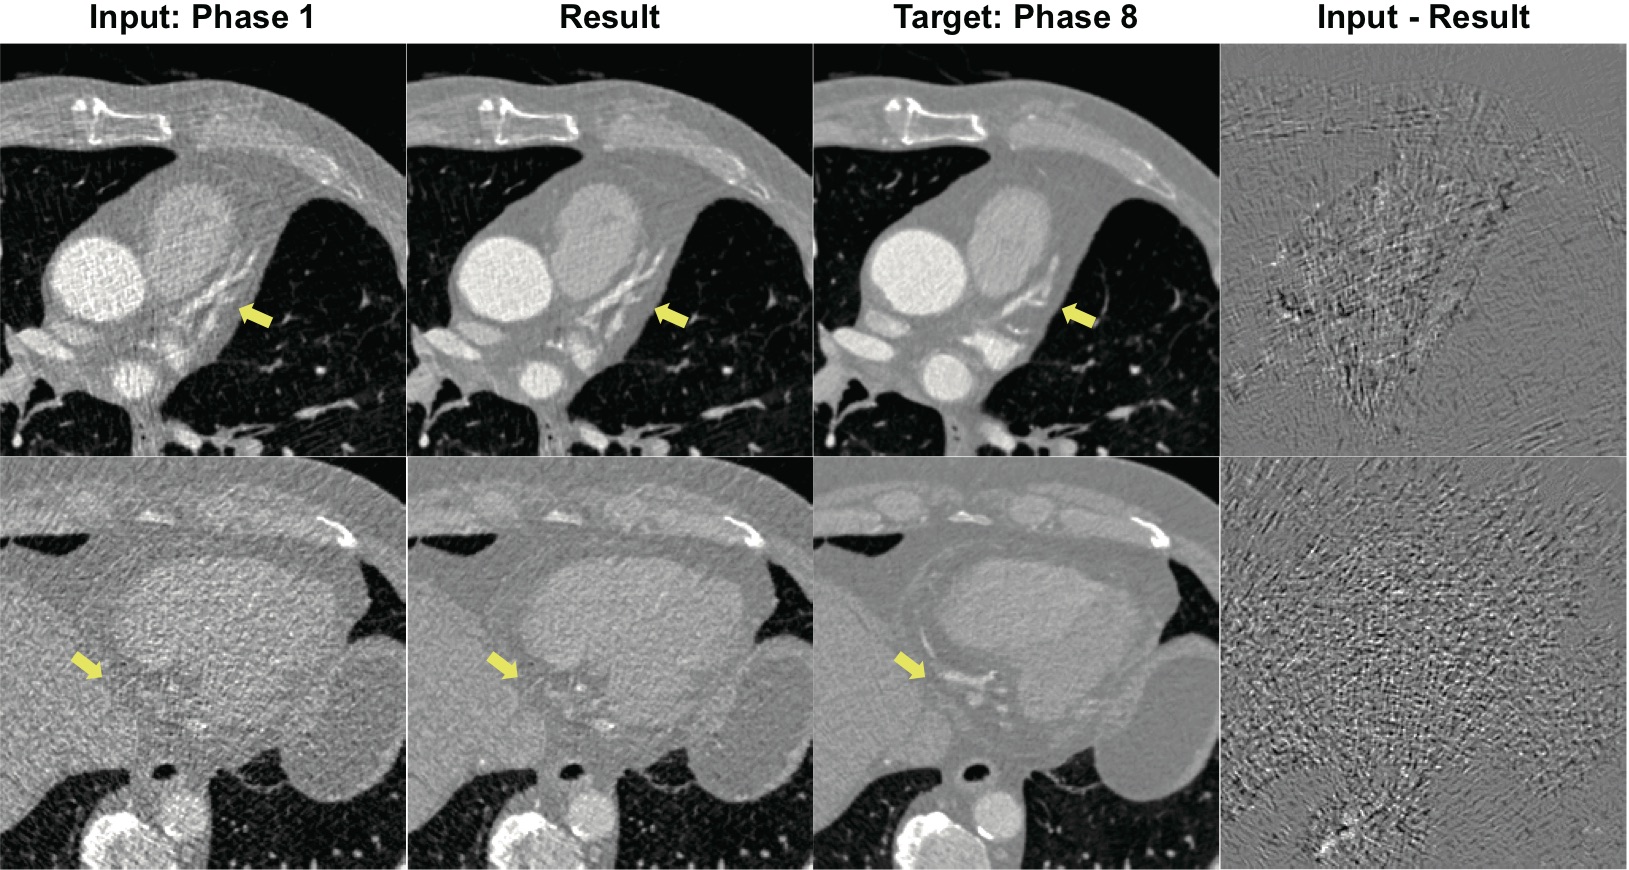

To verify the performance of the proposed method, we tested 50 cases from the dataset of mitral valve prolapse patients which were not used in the training session. Also, we tested 50 cases from the dataset coronary artery disease patients which were not used to training the network. The results are described in Fig. 5 and 6, respectively. Each row indicates the different patient case, and the restoration results from the first column are shown in the second column. The input low-dose CT images are from phase 1 and the target routine-dose images are from phase 8. Due to the cardiac motion during CT scanning, the shape of the heart and image intensity from the contrast agent are different at the two phases. Distinct differences are indicated by the yellow arrows in the images. The denoised results showed that the proposed method is good at reducing the noise in the input CT images while the texture information and edges are still intact. The difference images showed that the proposed method did not change the detailed information and only removes noise from the input CT images. The proposed method is robust to the type of heart disease as confirmed in another disease cases in Fig. 6. Results showed that the network does not create any artificial features that can disturb the diagnosis while maintaining the crucial information.